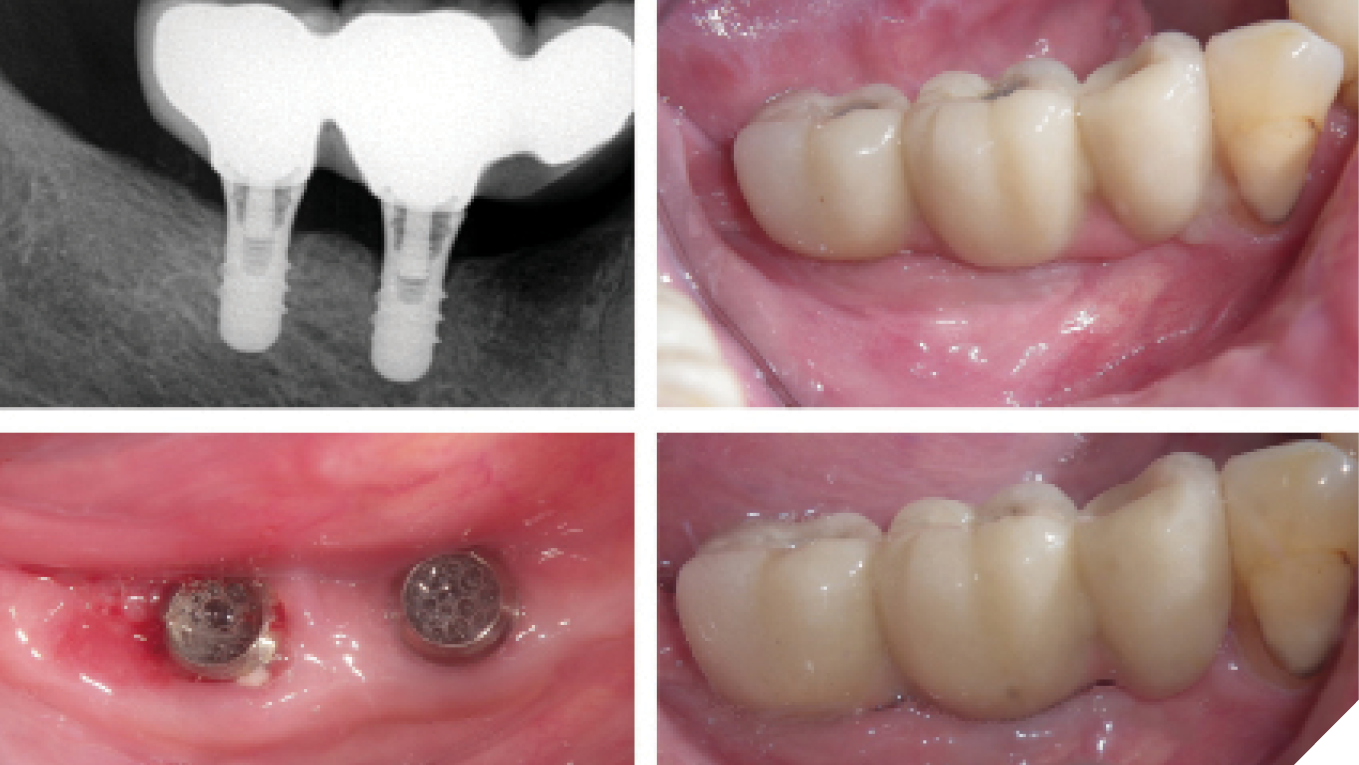

Current management strategies for peri-implant diseases

Dental implants have become a widely accepted solution for restoring both function and esthetics in partially or fully edentulous patients, through the use of either fixed or removable prostheses. Systematic reviews have consistently demonstrated high survival rates for both implants and prosthetic components, with an overall success rate of approximately 94.6%.1,2 However, peri-implant diseases remain … Read more